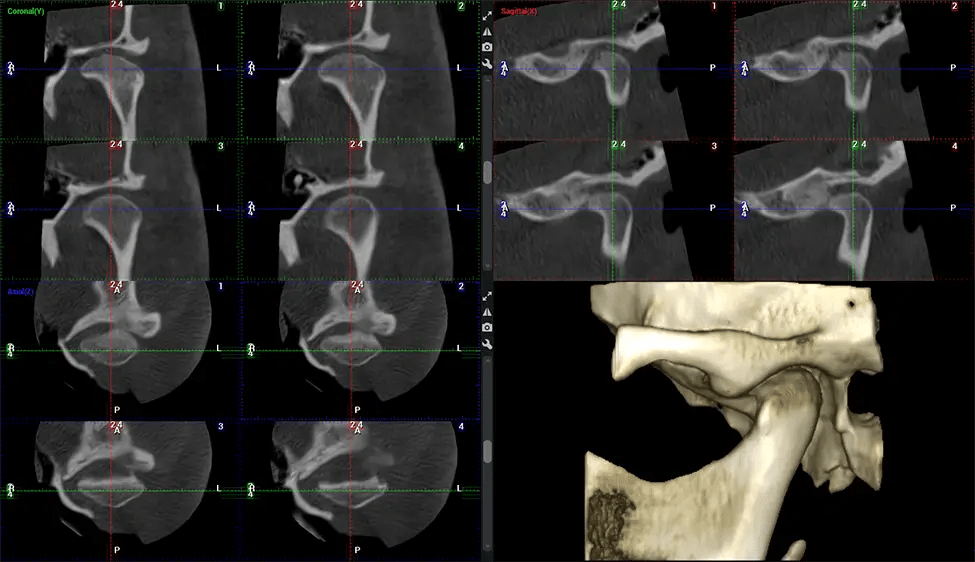

Cone Beam Computed Tomography (CBCT) is an advanced imaging technique used in dentistry and maxillofacial surgery to obtain detailed 3D images of the oral and maxillofacial structures. At Dr G Dental Studio, our CBCT scanners utilize a cone-shaped X-ray beam and a specialized detector to capture images from different angles. A computer then combines these images to create a 3D representation of the patient’s oral anatomy.

The patient is first positioned in the CBCT scanner, which typically consists of a rotating arm that houses the X-ray source and a detector. The patient’s head is immobilized to ensure accurate image capture. The X-ray source and detector rotate around the patient’s head, capturing various X-ray images from multiple angles. As the X-ray source rotates, it emits the cone-shaped X-ray beam towards the detector. The detector captures the X-ray images, which are then processed by the CBCT software.

After the scanning process, the captured X-ray images are processed by the CBCT software, which applies algorithms to reconstruct a detailed 3D image of the scanned area. The software compiles these individual X-ray images and creates a digital 3D representation of the patient’s anatomy. The reconstructed 3D CBCT image can be viewed and analyzed by the dentist or radiologist. This image can be manipulated, rotated, and zoomed in or out to examine specific structures and evaluate the patient’s condition.